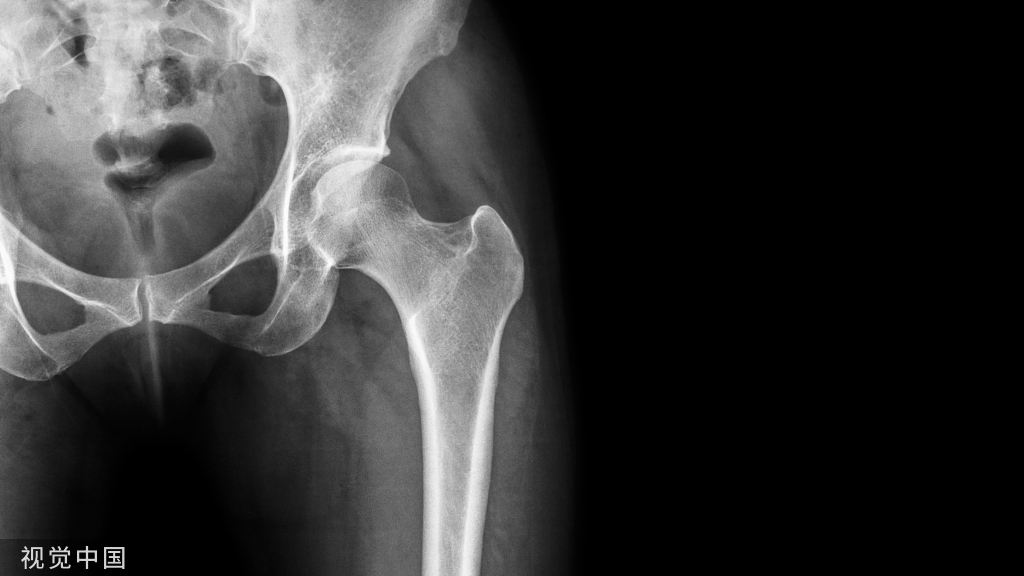

术后立即肩部x线片显示,锁骨骨折切开复位和Knowles针内固定后,肩锁关节(ACJ)明显移位。根据Rockwood分型诊断为V型ACJ脱位